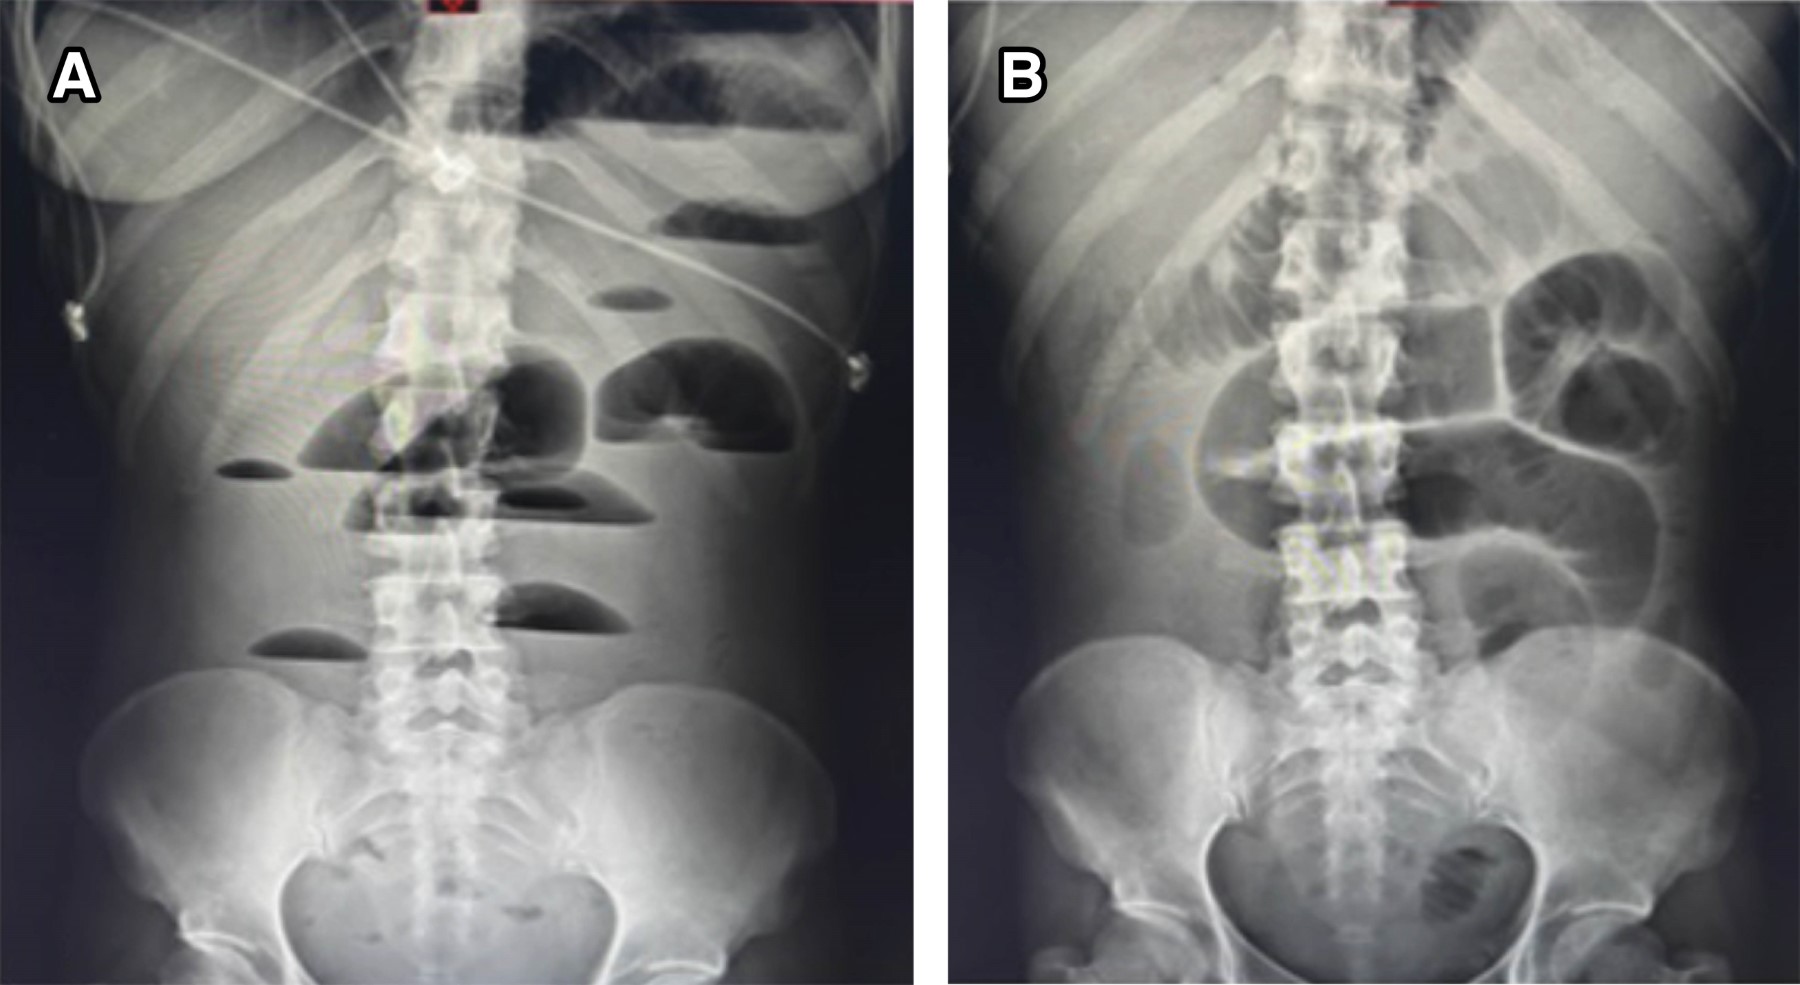

Figure 2